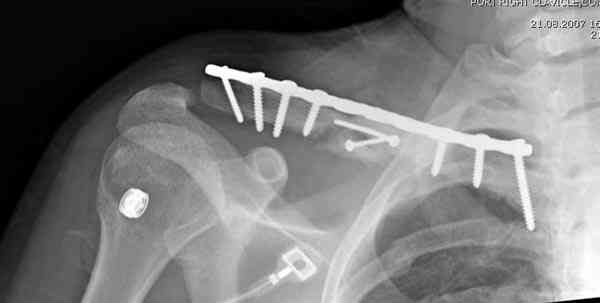

Консервативное лечение, через 8 мес. операция Rockwood pin с костной пластикой в нашем городе другим врачом. После 8 недели падение, гвоздь удален оперирующим хирургом, больная направлена к нам. Фиксация реконструктивной пластиной с трикортикальным графтом, добавлен BMP-2. Для стабилизации фиксацию провели через акромион.

Вот уже два месяца больная также продолжает жаловаться на боли, буквально на днях удалили акромиальную часть пластины с специальной пилой с алмазным покрытием для медицинского металла. До сих пор судьба ложного сустава неизвестна....